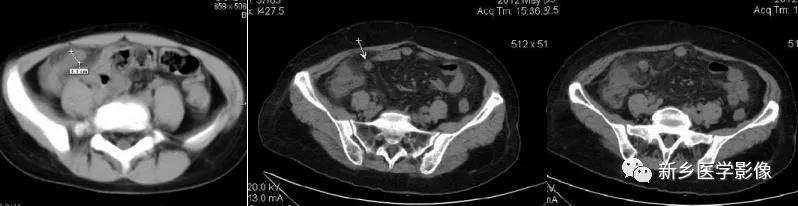

(2)CT:阑尾扩张,管径>6mm,壁增厚,增强强化。阑尾周围炎,周围(脂肪)“条纹征”即周脂肪内斑点/条纹状模糊英、局部筋膜增厚、系膜密度增高等。阑尾粪石,其他有盲肠增厚、阑尾周液体积聚、“箭头征”(肠道内造影剂汇集在盲肠尖端(阑尾起始部)形成箭头样或鸟嘴样改变)。

(2)CT:类似急性阑尾炎。阑尾扩张(管径>6mm)、阑尾尖端增厚、粪石、网膜系膜组织密度增高粘连、淋巴结肿大、“箭头征”、脓肿、蜂窝织炎、积液

(2)CT:右下腹/盆腔囊性肿块,壁薄或厚,增强环形强化,内部可见粪石;也可为边界不清、密度不均软组织影,强化不明显。肿块与盲肠关系密切,与周围结构粘连,内可见小气泡/气液平面。临近肠曲反射性淤积,可伴气液平面。